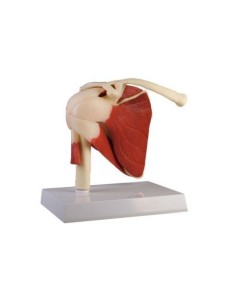

Modèle anatomique fonctionnel de la coiffe des rotateurs 3B Scientific W42005